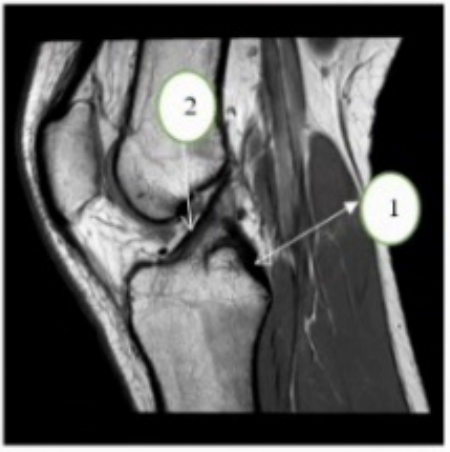

Key for 23-24 A medial meniscus B. lateral meniscus C. Tibia D. Fibula

Patient comes in with Hx of MM tear, which anatomy part will you scan?

a. Hip

b. bony pelvis

c. knee

d. ankle